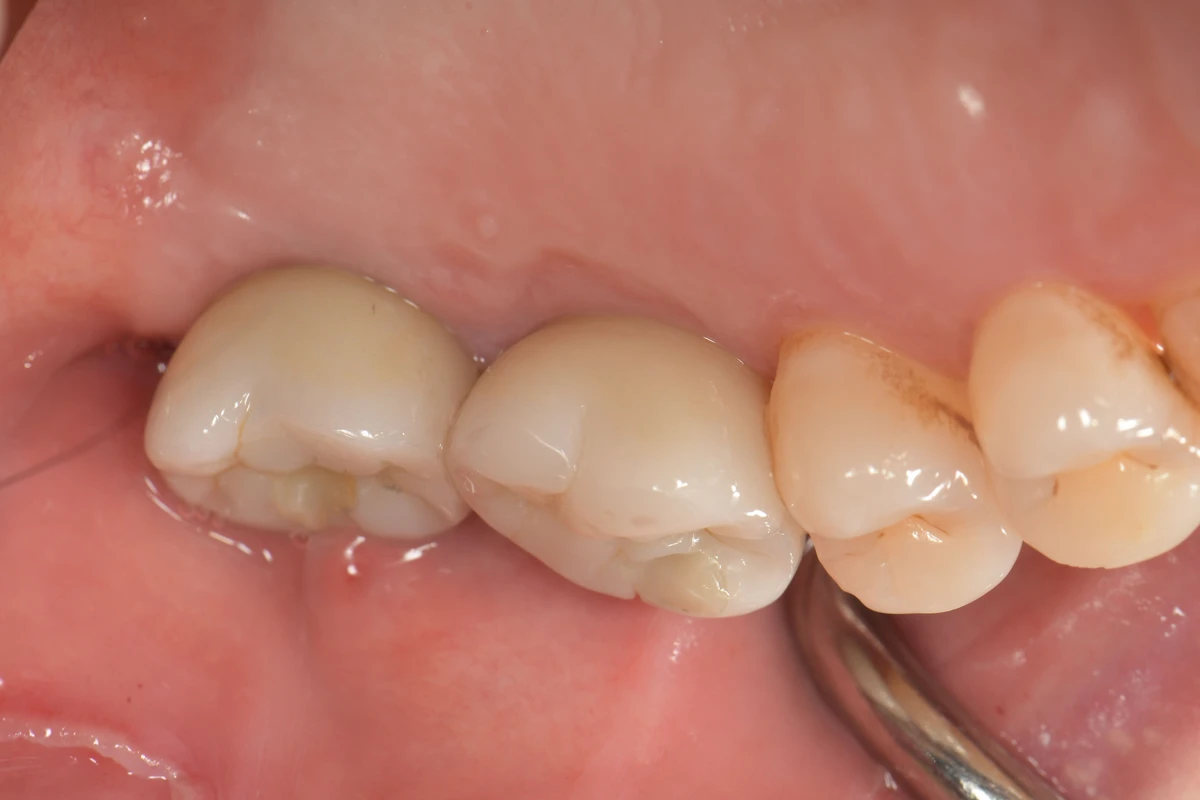

醫師了解病人的擔憂後,特別擬訂重建牙齒治療計劃。拔除病人的2顆牙齒後,隨即進行「齒槽脊保存手術」,並保留齒槽脊最大化的寬度和高度。後續植牙的等待過程中,積極安排全口牙周病治療,讓病人無需再進行大範圍補骨手術,順利在右側上顎缺牙區完成植牙重建治療,也恢復健康的咬合功能。

拔牙即刻做齒槽脊保存手術,順利以2顆植牙假牙做重建。(圖片來源:奇美醫院)

李芳欣表示,在進行拔牙手術前,除了告知醫師自身的健康狀況與用藥情況外,了解後續假牙製作方式及美觀需求也是關鍵步驟。齒槽脊保存術不僅能保持齒槽脊的形態,還能有效避免拔牙後牙齦和骨頭塌陷,從而維持牙齒的美觀和功能。

齒槽脊保存術對於有計畫進行植牙的病人來說,能有效提升植體穩定性和成功率。不過也要注意,此手術雖然能減少骨頭吸收,但補骨量仍有其限制。此外,與直接拔牙相比,此類手術需要等待骨粉癒合,因此植體植入的時間點會相對延後,病人需有心理準備。